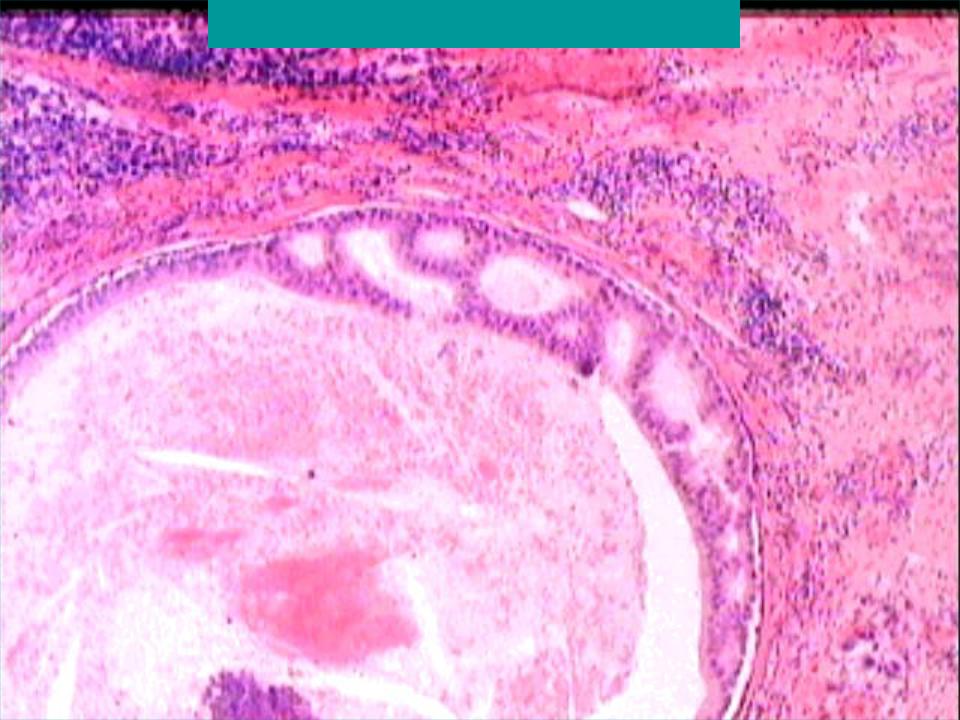

Исследование: микропрепарат молочной железы в медицине

Раздел: Снимки-откровения